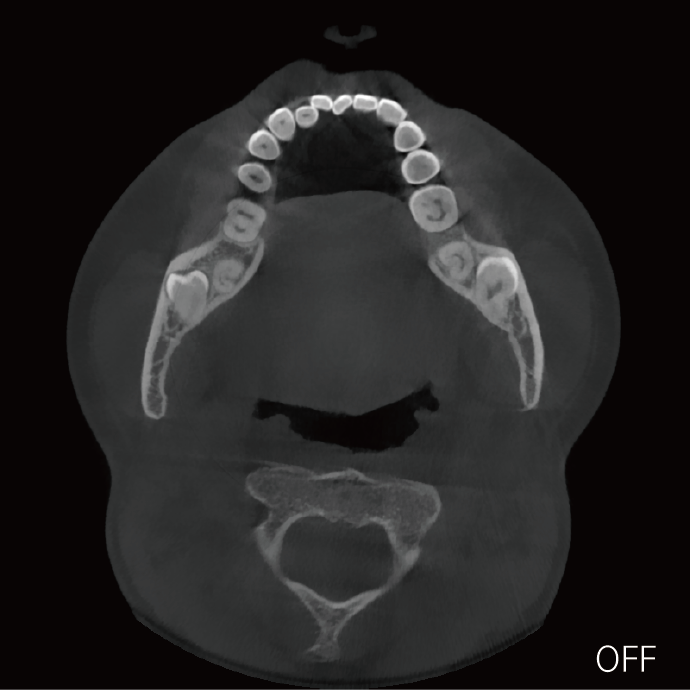

局部超清显示、 移动视野摄片

可根据临床需求任意调整成像区域大小实现局部超清三维显示

临床样片